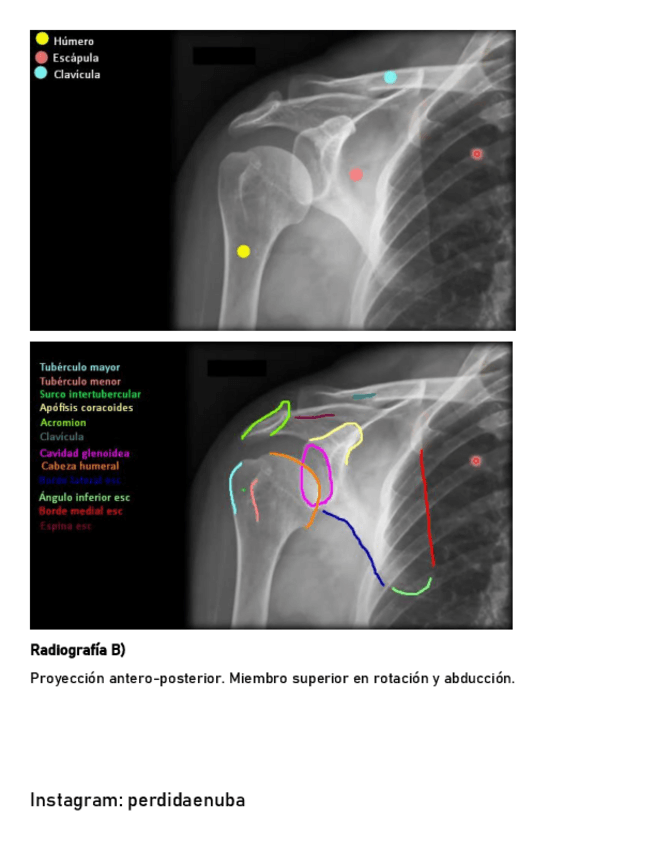

He publicado nuevos apuntes de 8º Cirugía General: CINTURA-PECTORAL-1.pdf